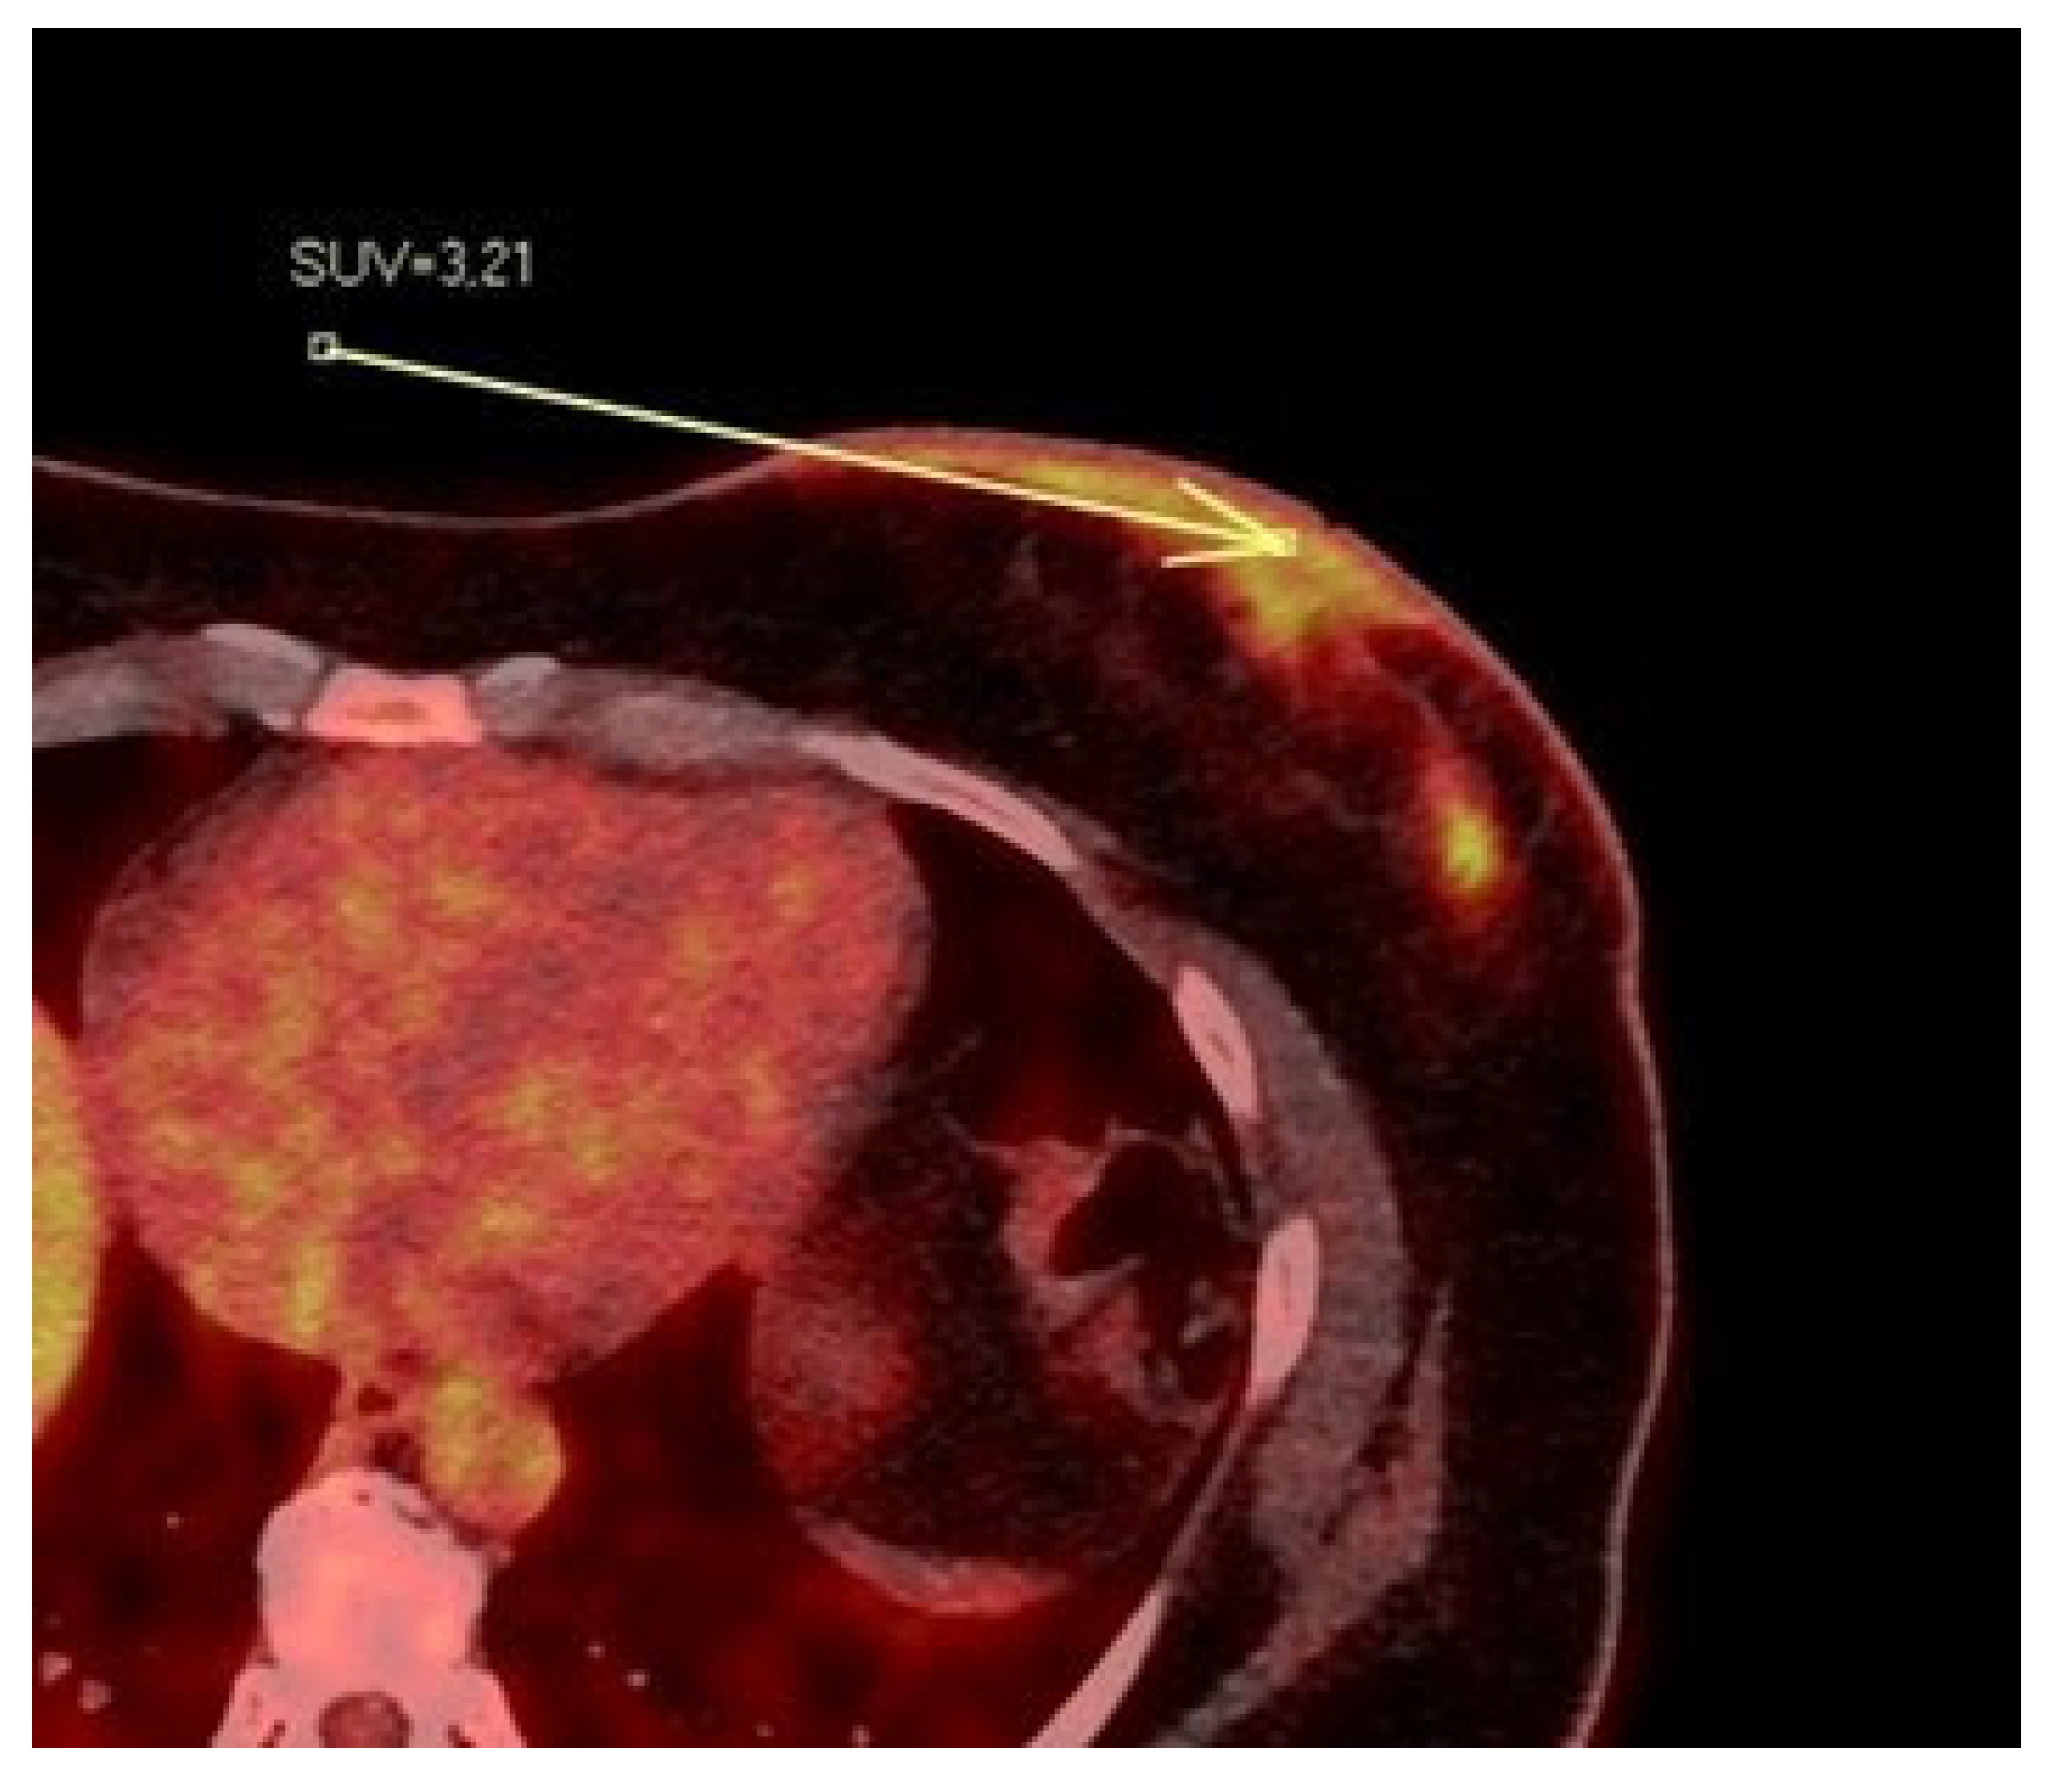

Figure 6.

Patient’s name R.M. During PET/CT, the pathological NAC-SUV value is measured at the base of the left nipple.

3.2. PET/CT Results: NAC-SUV Ratio

In our population, 33 women underwent PET/CT before starting neoadjuvant chemotherapy to assess skeletal status. For each patient, we quantitatively measured the NAC-SUV values in the malignant breast and the contralateral normal breast (Figure 6) in early-stage images (obtained one hour after radioisotope administration), delineating a three-dimensional volume of interest (VOI) over the NAC. The most representative image was selected, and the VOIs were carefully drawn to avoid including adjacent lesion areas, with the exception of the nipple presumed to be infiltrated based on imaging. We calculated the NAC-SUV ratio (R) by considering the ratio of NAC-SUV in the malignant breast to NAC-SUV in the contralateral normal breast. The NAC-SUV R was calculated only for early-stage images. The calculated mean SUV of pathological NACs was 3.59, while the mean SUV of contralateral normal NACs was 2.12. The calculated mean NAC-SUV ratio was 1.7.